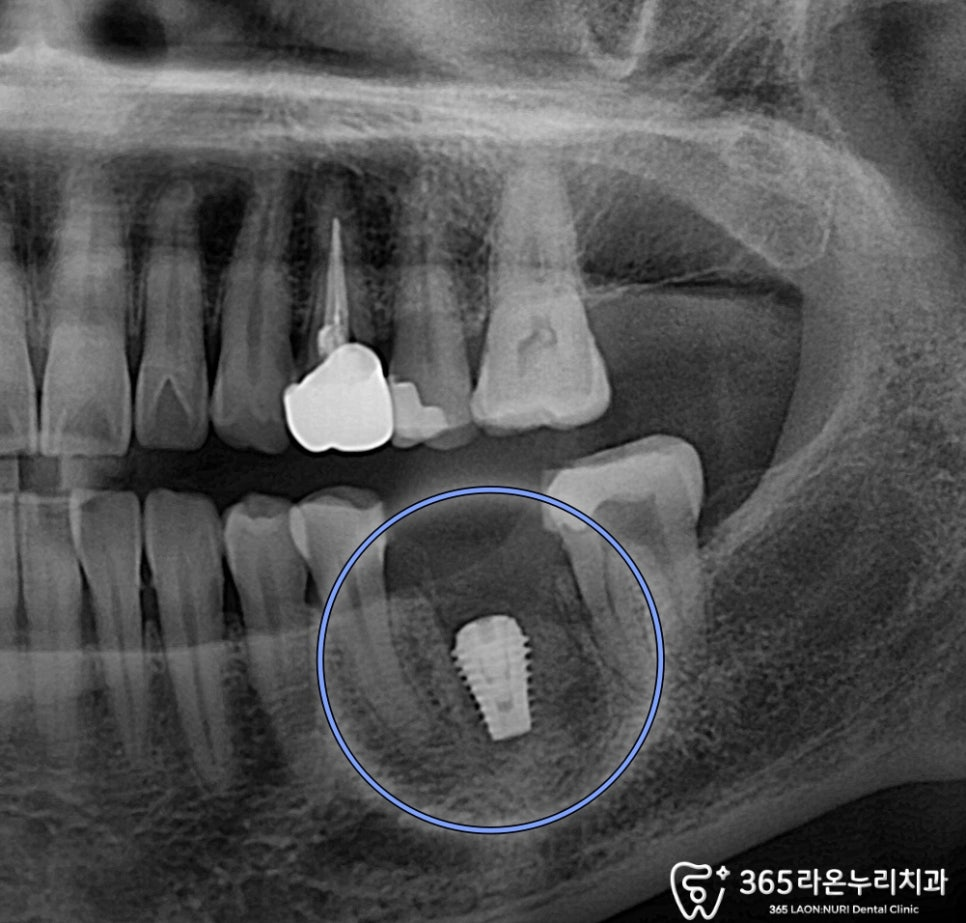

2025.02.13

그리고 픽스쳐와 뼈가 회복하는 동안

주변에 충치가 있던 치아는

근관치료 및 인레이 치료로 충치를 개선합니다.

임플란트 식립했던 부위도

안전한 수치가 나오게 되면

똑같이 인상채득을 해주고